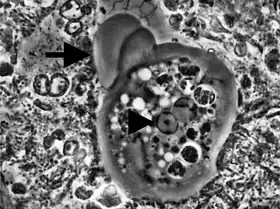

On ne connait que la forme végétative, très active, large de 12 à 150 microns, avec noyau de type Entamoeba, un ectoplasme bien différencié et un endoplasme contenant des leucocytes phagocytés[2] et, rarement, une ou deux hématies.

L'activité principale de l'amibe Entamoeba gingivalis dans les crevasses parodontales infectées, en plus de se déplacer, consiste à se nourrir des noyaux des globules blancs polymorphonucléaires neutrophiles. À la suite de l'adhésion du PMN et à son engourdissement, l'amibe pénètre le cytoplasme pour atteindre le noyau et littéralement succionner son contenu via la pression négative du pseudopode. Sa nourriture ainsi ingurgitée est digérée progressivement à l'intérieur de l'endoplasme. La phagocytose peut parfois se poursuivre pour plus de 20 noyaux ingurgités. Cette activité laisse en place un PMN énucléé, incapable d'accomplir son apoptose préprogrammée et probablement son activité NETS, qui sera déversé sur les tissus environnants entrainant des enzymes protéolytiques à partir des restes de cette cellule fantôme dès lors hors contrôle et capable alors de destruction cellulaire.